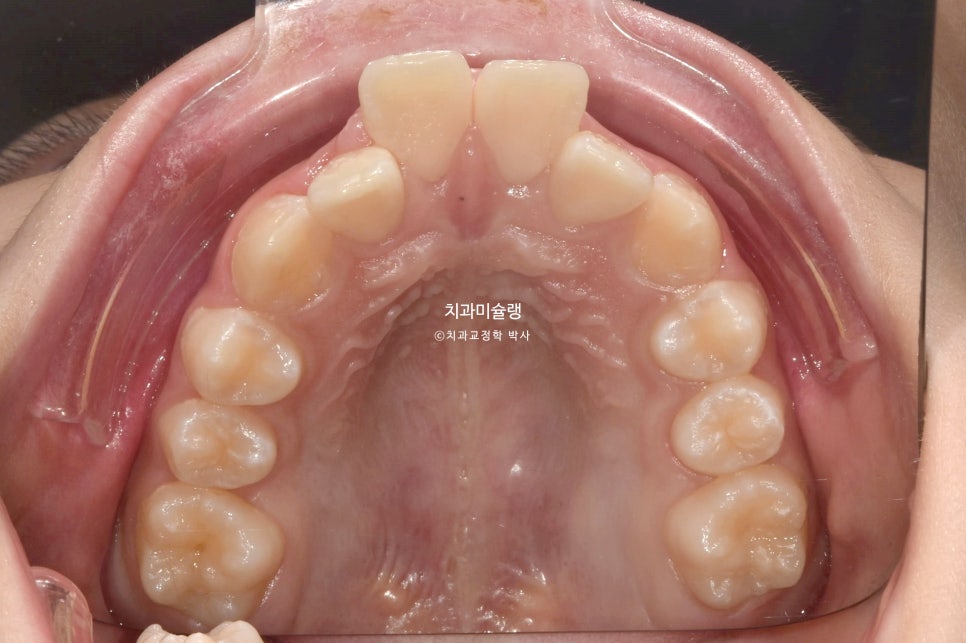

2023년 7월,

앞니 돌출과 삐뚤한 치아 때문에

교정치료를 위해 온 어린이 입니다.

아래앞니가 윗니에 가려 안보일 정도의 심한 과개교합입니다.

앞니가 튀어나온 돌출입니다.

좌우 교합관계가 모두 2급이며 특히 좌측이 더 심합니다.

아랫니도 삐뚤삐뚤 합니다.

유치가 남아있고 나이가 11세 미만이라 인비절라인퍼스트 어린이교정이 가능한 상황 입니다.